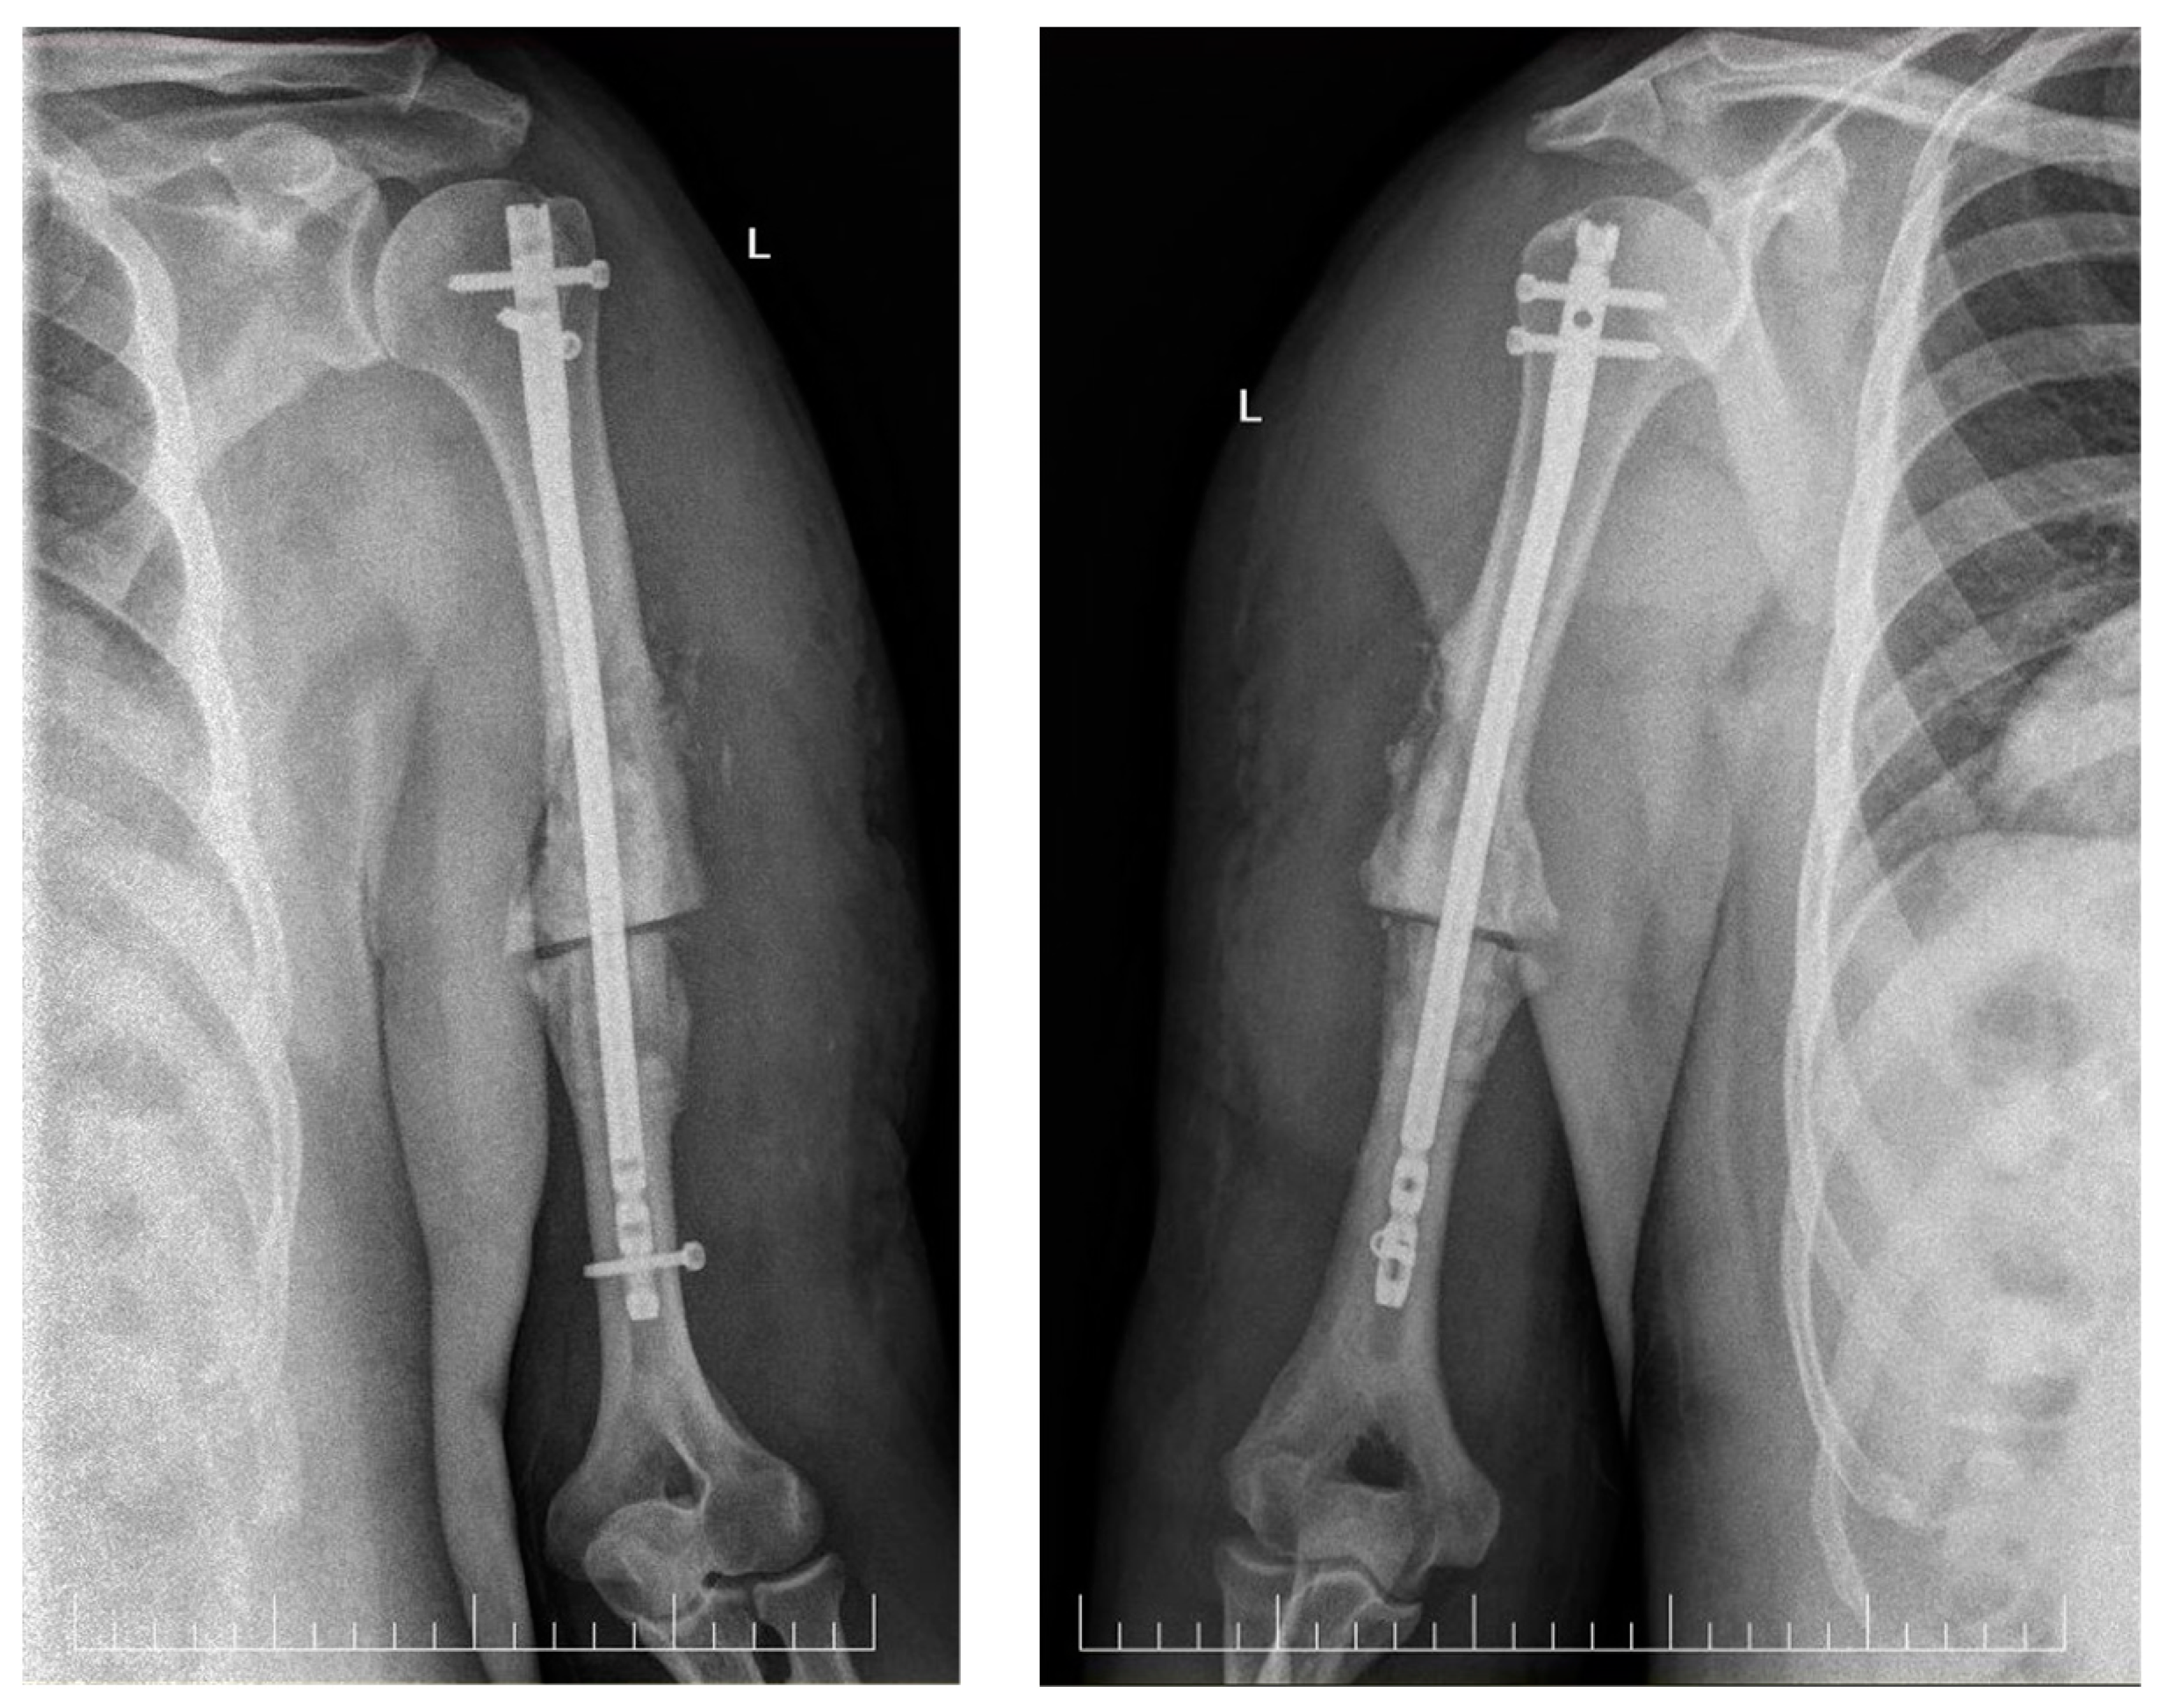

Anterograde Intramedullary Nailing without Bone Grafting for Humeral Shaft Nonunion Associated with Early Exploration of Secondary Radial Nerve Palsy: A Case Report

2. Case Report